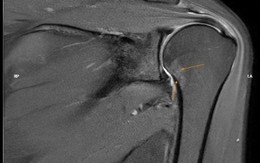

Sống khỏe 2025-02-03T15:31:00Người phụ nữ xuất hiện một dấu hiệu suốt 6 tháng và gặp khó khăn khi mặc áo, chải đầu nên đã quyết định đi khám để tìm nguyên nhân.

Có 1 dấu hiệu suốt 6 tháng, người phụ nữ đi khám, phát hiện khớp vai đông cứng